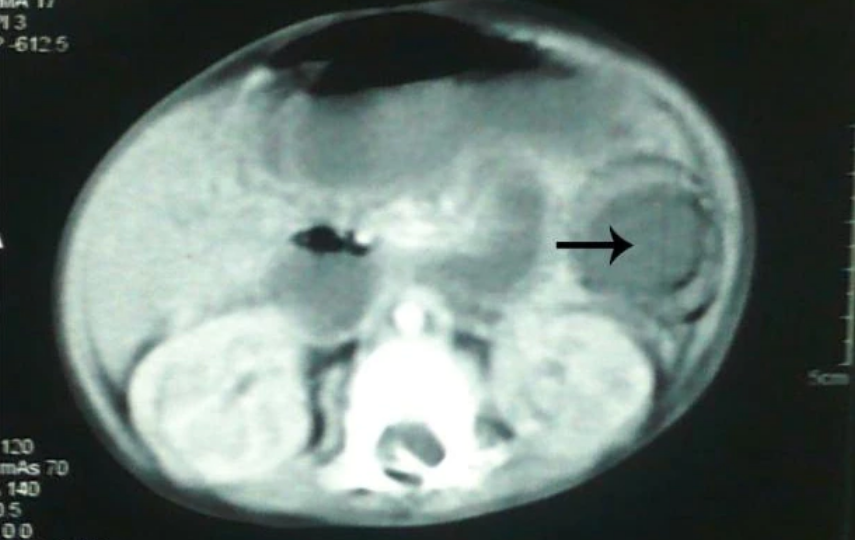

A six-month-old boy in Pakistan swallowed a brightly coloured “gel ball” in 2012, which caused a bowel obstruction.

He then suffered a “burst abdomen” after surgical removal, developed septicemia and died two days after a second operation.